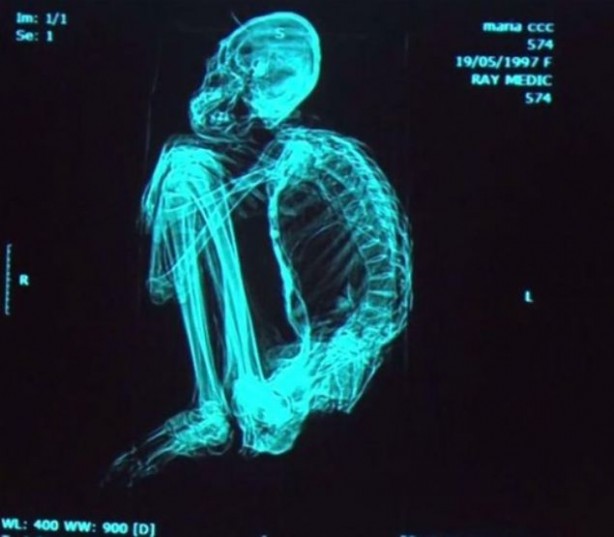

Peru'da bulunan ve el ve ayaklarında 3 parmağı olduğu belirlenen mumyanın dünya dışı bir varlık olup olmadığı araştırılıyor.

Peru’nun Nazca bölgesinde geçtiğimiz yıl yaz aylarında bulunan mumyayla ilgili incelemeler sürüyor.

İnce uzun bir kafatası ile üçer parmaktan oluşan el ve ayakları olduğu belirlenen mumyanın, farklı bir canlı türü ya da dünya dışı bir varlık olup olmadığı araştırılıyor.

Yapılan ilk testlerin sonuçlarına göre mumyanın, insanlarla aynı kromozom yapısına sahip olduğu ancak vücut yapısının hayli farklı olduğu belirlendi.